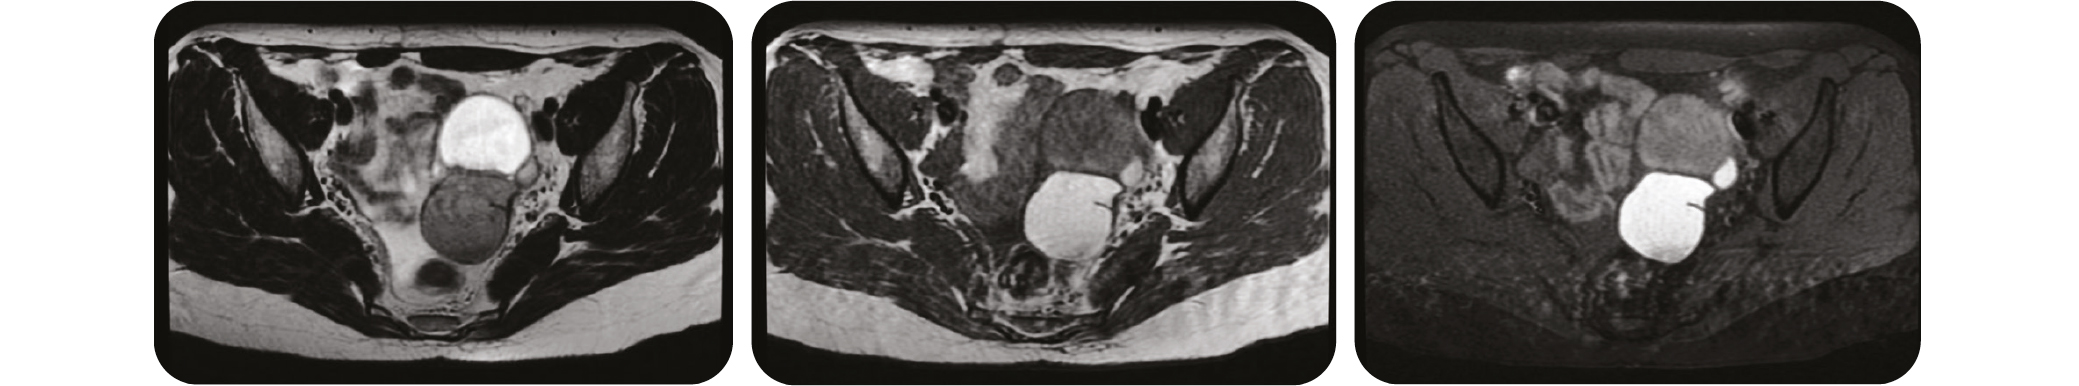

De gauche à droite : Axiale T2 / Axiale T1 / Axiale T1 FatSat => Comparer le signal entre un kyste liquidien en hypersignal T2 au-dessus de l'endométriome en hyposignal T2 et hypersignalT1 en dessous. (Source : Radiopedia)

Le signal IRM classique de l'endométriome est hypersignal T1 franc (supérieur à graisse), hypersignal T1 persistant sur les séquences après saturation de graisse et en hyposignal T2 (dans 95 % des cas, signal T2 assez caractéristique appelé « shadding »).